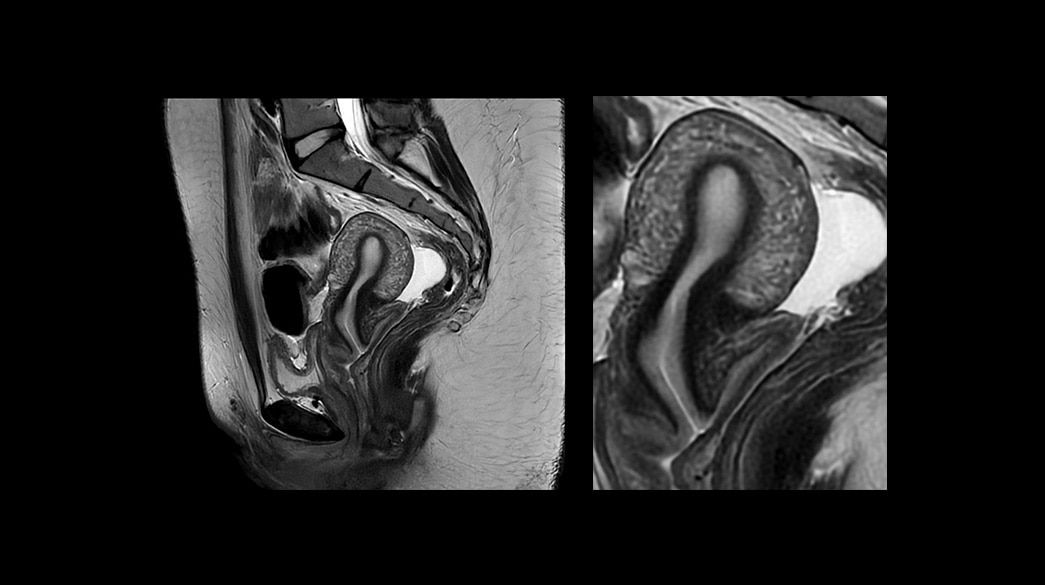

Consistent

Motion and distortion-reduced scans with high-resolution and contrast

Personalized

Comfortable, acoustic reduced imaging, added to any patient